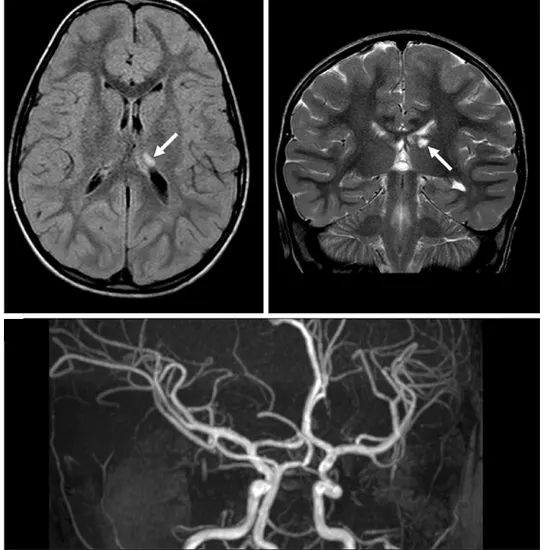

MRI of the brain is the imaging test to get detailed images of the tissues whereas MRA is the imaging test through which clear images are taken of the blood vessels to check blockage.

Both MRI and MRA are conducted to get clear images of the brain. MRI is done to check for brain abnormalities while MRAs are done to check narrowing or blockage of the blood vessels.

For the test, a patient is slipped under the MRI machine. Both MRI and MRA use magnetic fields, radio waves and a computer to get images. In MRA, a dye is injected to get a clear view of the blood vessels.